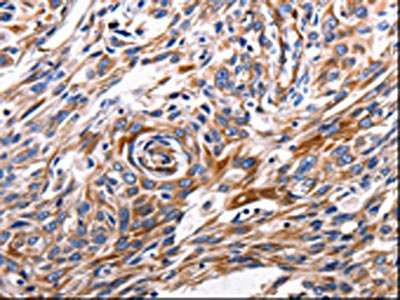

The image is immunohistochemistry of paraffin-embedded Human esophagus cancer tissue using CSB-PA025395(ACE2 Antibody) at dilution 1/200. (Original magnification: ×200)